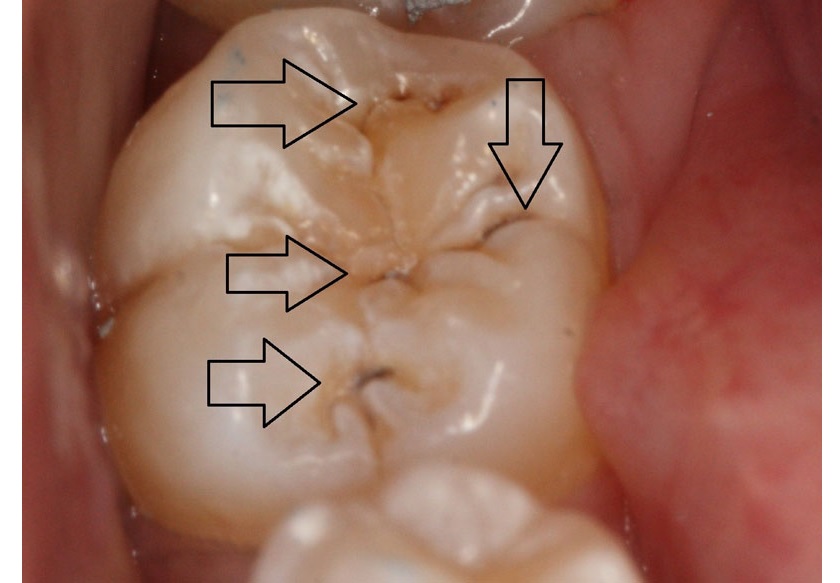

Trám bít hố rãnh phòng ngừa sâu răng tại các răng trong cùng

Sealant nên được áp dụng ở các răng quan trọng và có nguy cơ sâu răng cao nhất, thường là các răng hàm vĩnh viễn ở phía trong cùng (răng số 6, số 7). Tuy nhiên với những răng khác có hố, rãnh sâu hay ở trẻ vệ sinh răng miệng không tốt thì cũng nên làm Sealant để giúp trẻ giảm nguy cơ sâu răng.